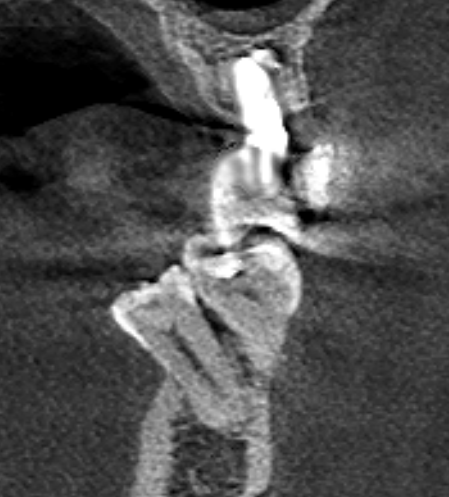

Александр9 Опубликовано 26 ноября, 2021 Поделиться Опубликовано 26 ноября, 2021 Мне предлагают удалить дистопированный 35 зуб, но он мне не мешает. Меня только пугает, что из-за него "страдают" соседние зубы. И если его не удалить, то со временем придется удалять и их. Подскажите пожалуйста, оправданно ли его удаление с целью улучшения "жизни" соседних 34, 36 зубов? (при условии нормальной гигиены (ирригатор, зубные нити) и лечении кариеса). Ссылка на комментарий